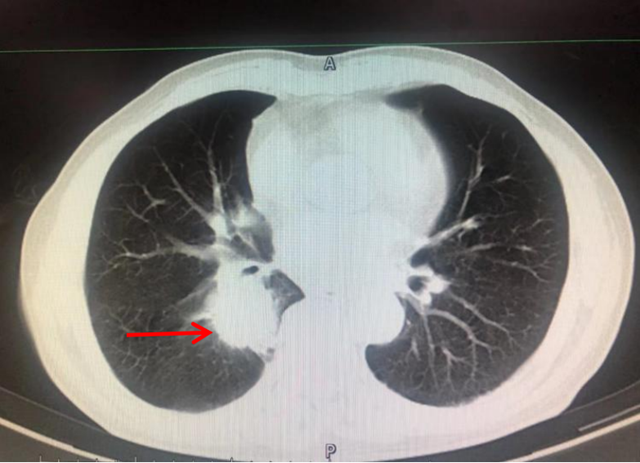

几天前,在西藏连上两个夜班的熊先生开始出现头晕头痛,吃完一盒止痛药后程度不减反增,并出现恶心呕吐、四肢麻木的症状,在当地医院就诊后没有找到病因,于是赶紧乘飞机回到家乡泸州。  连续几天的头痛失眠、呕吐脱水、全身麻木无力等,让熊先生的思维出...